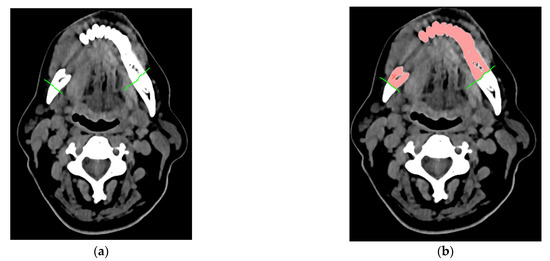

2.1. Procedure of the Reconstruction of Geometry and Modelling Templates